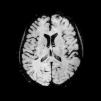

A 19-year-old male presented with asthenia, abdominal pain, vomiting, fever, jaundice, and rash. The patient quickly progressed to severe shock, purple lower limbs and toes necrosis. The diagnosis of Rickettsia spp (gene regions surveyed gltA (TaqMan) and internal control of the human RNAse P reaction) was made by PCR (polymerase chain reaction) of serum sample. Serial serology, with indirect immunofluorescence, also turned out positive with increasing IgG titers, initially <1/64 and then >1/256 two weeks later. The patient went on to present nystagmus and conjugate eye deviation. Magnetic resonance imaging (MRI) identified: multiple foci of marked hypointensity on susceptibility weighted imaging (SWI), evidenced in the corpus callosum, deep white matter, bilateral basal ganglia, thalamus and middle cerebellar peduncles, compatible with hemosiderin deposits, possibly petechial hemorrhages (Fig. 1). Foci of hyperintensity were observed on T2/FLAIR weighted images in the semiovale centrum, deep white matter and periventricular regions (Figs. 2 and 3). The patient was treated with chloramphenicol but progressed with extremity necrotic lesions, requiring bilateral transmetal amputation of toes and at the proximal phalanx of second, third, fourth, and fifth fingers of the right hand. He was discharged after 55 days of hospitalization for outpatient follow-up.

Dissemination to the central nervous system (CNS) occurs by hematogenous spread, with invasion of arterioles and capillaries, leading to inflammation and rupture of the blood–brain barrier. The possible findings on MRI include meningeal enhancement, varying degrees of swelling and periventricular and subcortical infarction, secondary to vasculitis, which tend to occur in a perivascular distribution, as observed in this case (which can mimic demyelinating disease).2,3 The CT scans of the head can be normal or show diffuse white matter changes, sulcal effacement and/or focal hypodensities consistent with infarctions.4 However, MRI is the exam that better characterizes CNS involvement in this entity, evidencing both multifocal hemorrhages and the foci of white matter changes due to vasculitis.